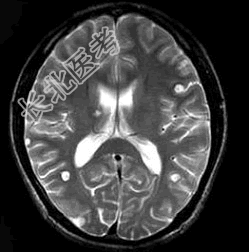

- 单项选择题患者,男, 29岁。头痛不适半个月。MRI扫描如图示。据此可作出下列最可能的诊断是 ( )

A、脑囊虫病

B、脑弓形虫病

C、脑结核

D、脑转移瘤